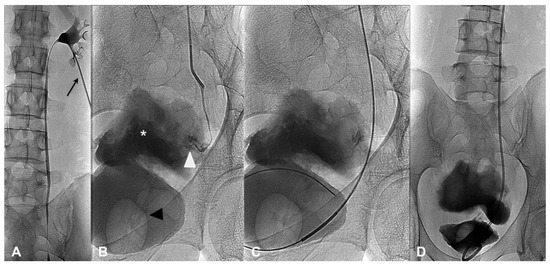

2.3.1. Anterograde Approach

All procedures were performed with the patient in the prone position. Using US guidance, a Chiba needle was used to access the renal cavity, preferably from the lower or middle posterior calyx. An 18 G needle (Chibell, Byopsybell, Mirandola, Modena, Italy) was used in markedly dilated, and a 21 G needle (Accustick, Boston Scientific, Marlborough, MA, USA) in mildly or non-dilated collecting systems. After the placement of a short introducer (5-F, Cordis, Miami, FL, USA), a descending pyelography study was performed to confirm the presence and the site of the leakage. Subsequently multiple attempts were usually performed to cross the damaged tract with a 0.035-inch hydrophilic guide-wire (Glidewire, Terumo, Tokyo, Japan). In case of successful crossing, over a stiff guide (Amplatz, Cordis, Miami, FL, USA) a plastic 8-F double-J stent (Flexima Ureteral Stent, Boston Scientific, Marlborough, MA, USA) was placed (Figure 1A–D). An 8F nephrostomy tube (Boston Scientific, Marlborough, Massachusetts, USA) was maintained in all cases.

Figure 1. (AD)—A successful anterograde approach. Right descending pyelography (A,B) performed using a 5 Fr introducer (black arrow) proves a lesion (white arrow head) of the distal third of the right ureter associated with urinoma (white asterisk); the bladder is distended by contrast medium injected through a urinary catheter (black arrow head). (C) A hydrophilic guidewire is advanced in the bladder with a catheter through the ureteral distal stump and a double-J stent (D) was implanted and correctly positioned.